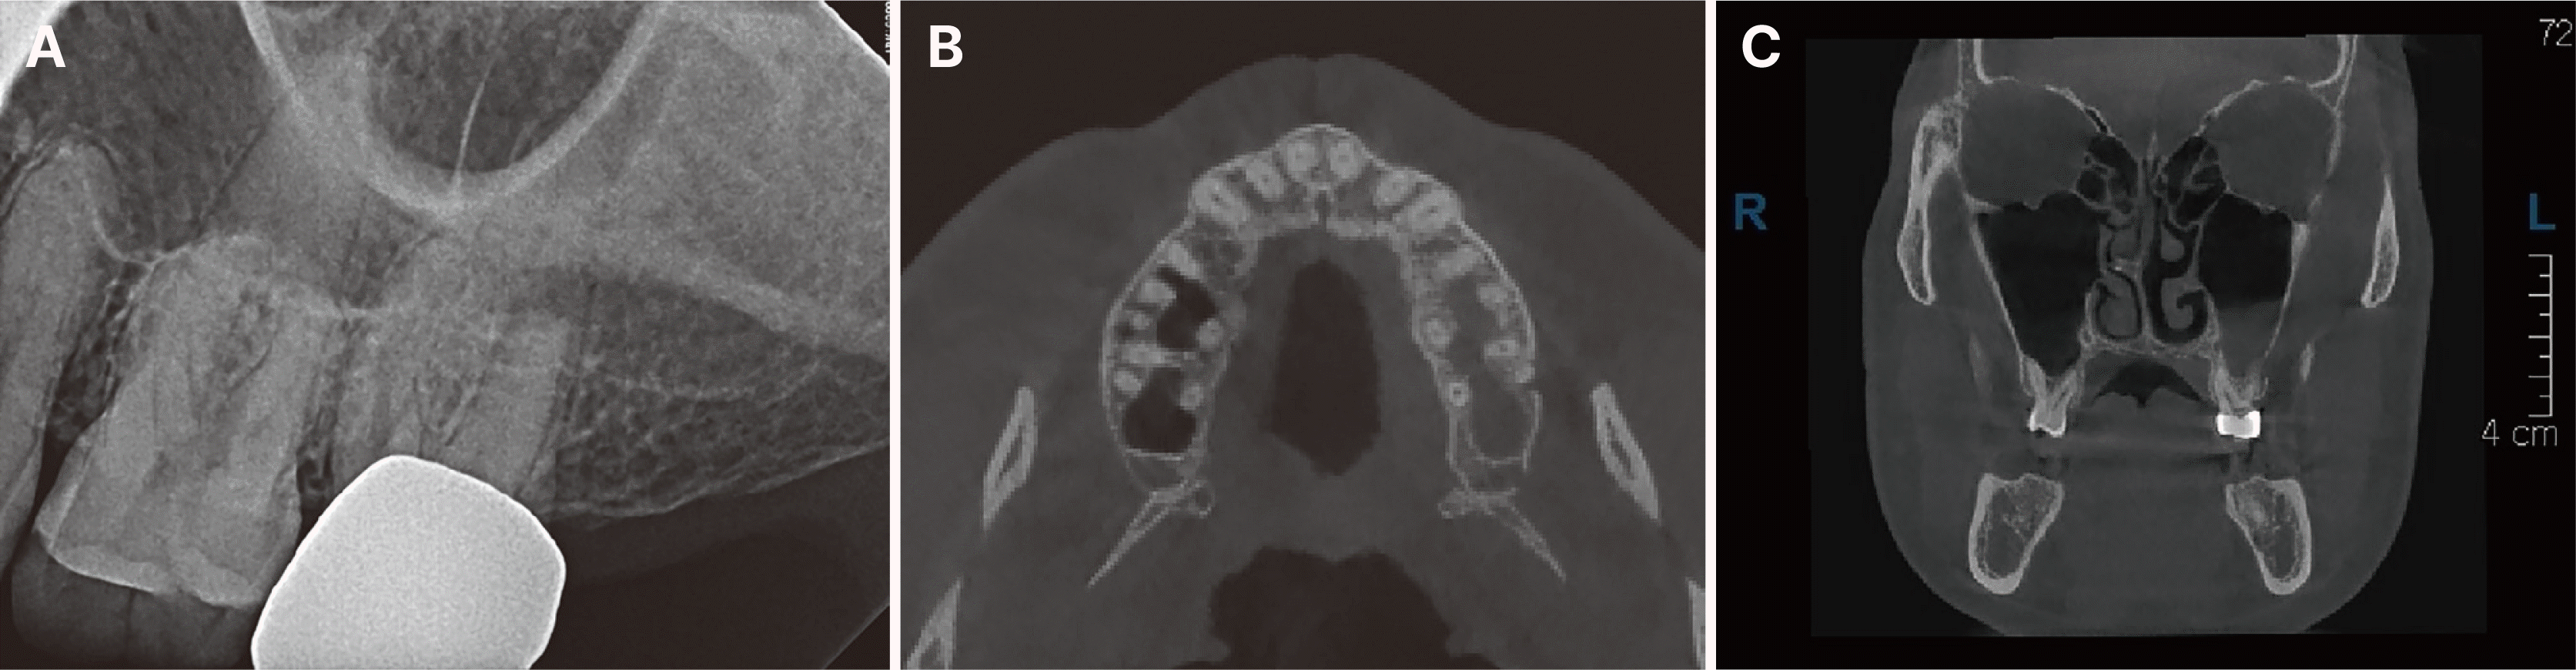

45세 남자환자가 상악 좌측 어금니 부위 통증 및 코에서 노란색 고름이 나온다는 주소로 이비인후과 경유하여 원광대학교 대전치과병원 구강악안면외과에 내원한 뒤, 상악 좌측 제2대구치 평가를 위해 보존과로 의뢰되었다(Fig. 1A). 환자는 이비인후과에서 한달 동안 항생제를 포함한 투약 치료를 했었다고 말하였다. 환자는 해당 치아가 골드 크라운으로 수복된 상태로, 크라운 제거 없이 크라운 상방으로 치과의원에서 10회 이상 근관 소독을 진행하였으나 증상 차도가 없었다. 임상 검사상 상악 좌측 제2대구치 타진 및 저작검사에 양성 반응 보였으며 Cone-beam computed tomography (CBCT) 상 원심 협측 치근에 치근단 병변 및 좌측 상악동 점막 비후가 관찰되었다(Fig. 1B and 1C).

Fig. 1

Preoperative radiograph of maxillary left second molar. (A) Pericapical view, (B) CBCT axial view, (C) CBCT coronal view.